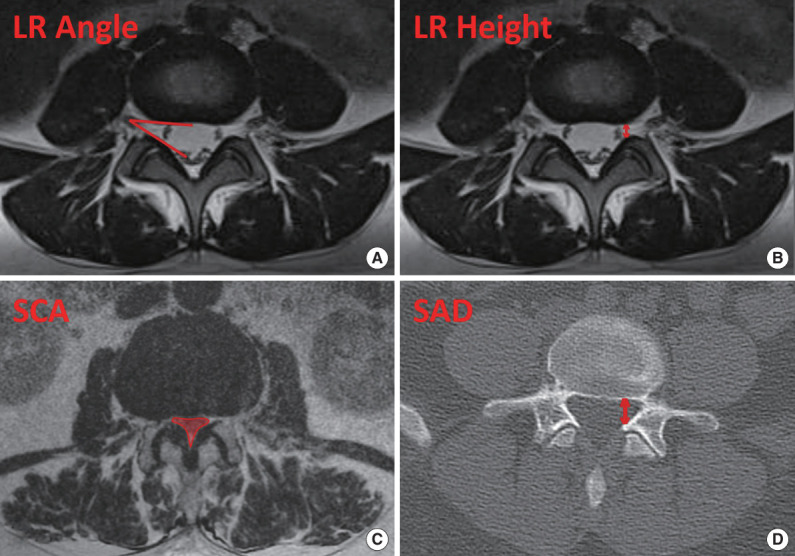

Methods: Patients with single-level lumbar spinal stenosis without instability were included in this multicenter retrospective study. Visual analogue scale (VAS) scores for each extremity, VAS back pain, and Japanese Orthopaedic Association (JOA) scores at preoperative and postoperative 1st, 6th, and 12th months were used as clinical outcome measures. In order to compare the radiological results of the patients, bilateral superior articular distance (SAD), bilateral lateral recess height (LR height), bilateral lateral recess angle (LR angle), and cross-sectional spinal canal area values were measured.

Results: Eighty patients in the UBELD group, 73 patients in the MEL group, and 62 patients in the PELD group were included in the study. There was a statistically significant improvement in VAS scores and JOA scores in all groups compared to the preoperative period. At the 12th month postoperatively, the highest lateral decompression values on the approach side were determined as MEL (SAD: 4.1 mm, LR angle: 38.8°, LR height: 4.0 mm), followed by UBELD (SAD: 3.6 mm, LR angle: 36.2°, LR height: 3.3 mm) and PELD (SAD: 3.0 mm, LR angle: 21.7°, LR height: 2.3 mm), respectively. For the contralateral side, the highest lateral recess decompression values were listed as UBELD > MEL > PELD.